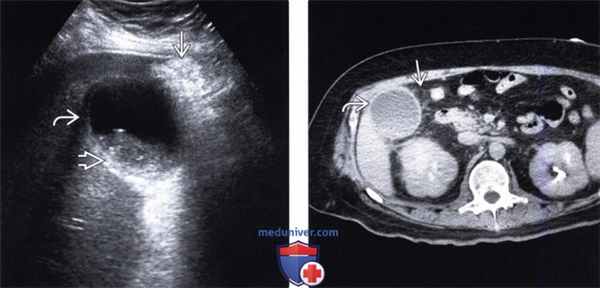

(Левый) При остром холецистите на поперечном УЗ срезе визуализируются смещающиеся книзу под действием гравитации конкременты желчного пузыря и сладж. Обратите внимание на утолщение стенки желчного пузыря и воспаленную эхогенную жировую клетчатку с медиальной стороны.

(Правый) Этот же пациент. Аксиальная КТ с контрастным усилением. Определяются растянутый желчный пузырь с утолщенной стенкой В, смещающиеся книзу под действием гравитации конкременты и сладж. Обратите внимание на исчерченность перипузырной жировой клетчатки.